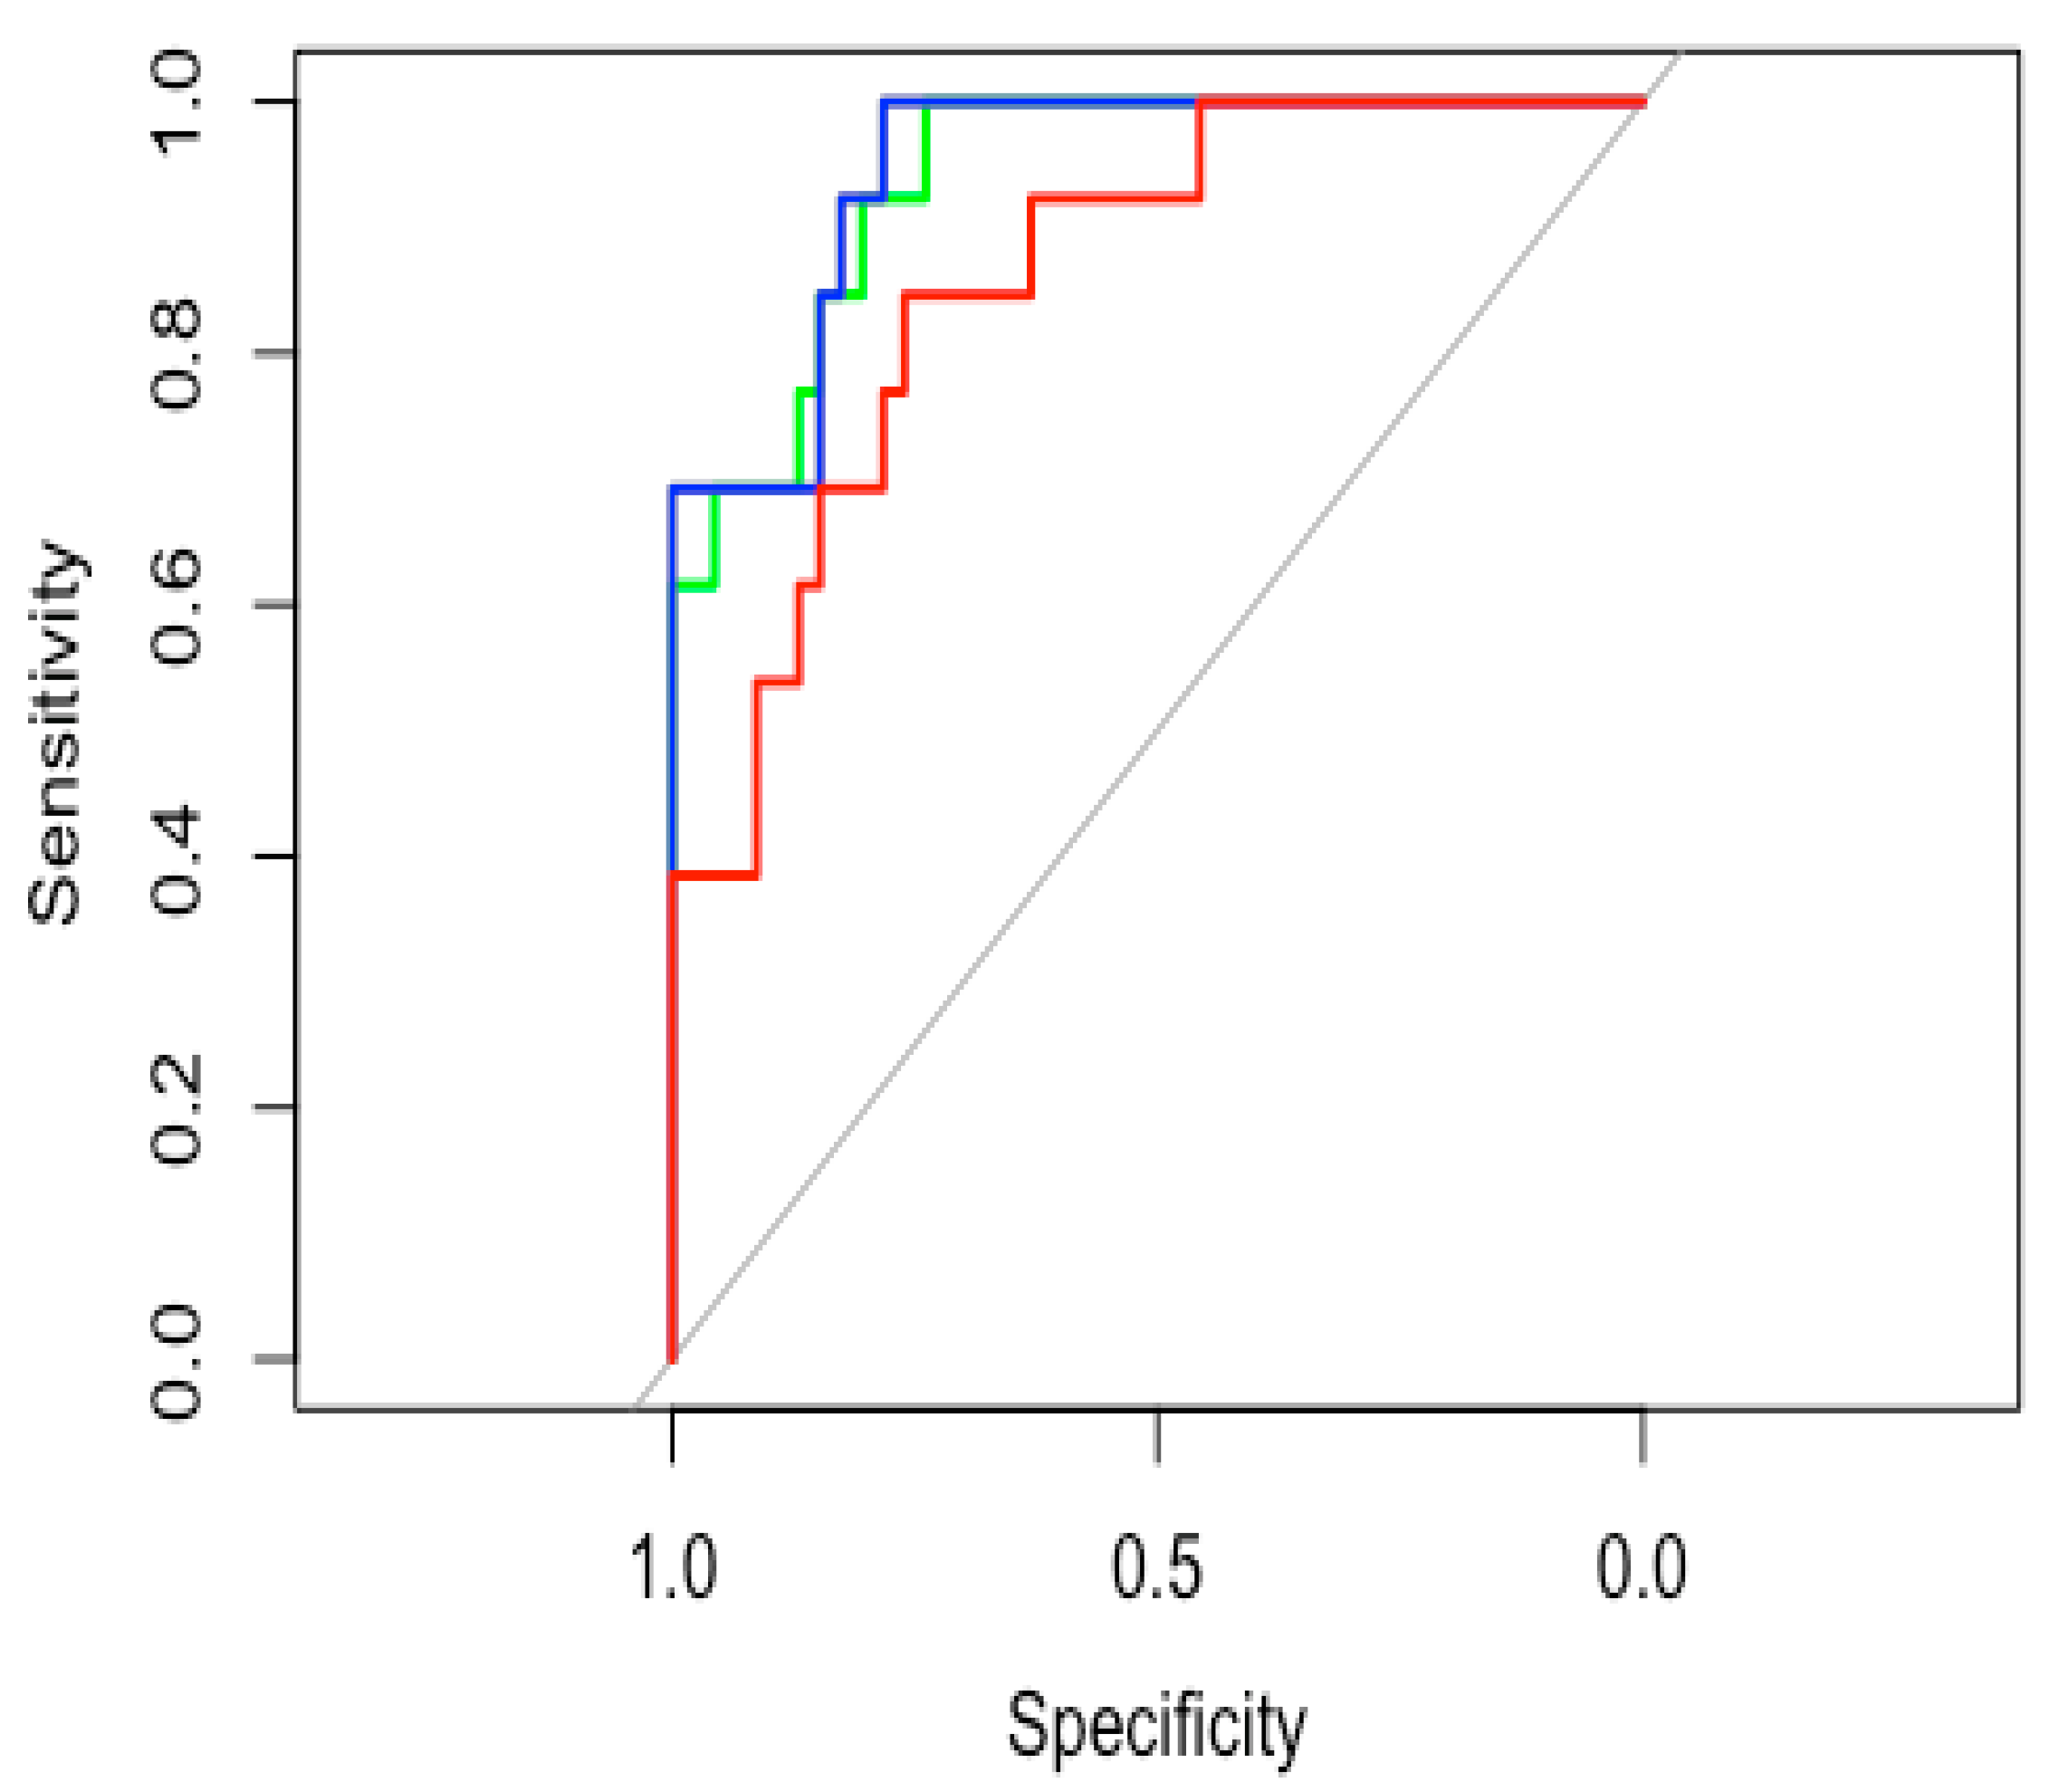

3.4. Model Accuracy Estimation

3.5. SMOTE Analysis